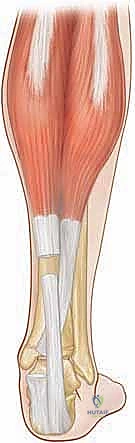

وتر أخيل (الوتر العقبي - Achilles Tendon)

يُصنف وتر أخيل كأقوى وأسمك وتر في جسم الإنسان على الإطلاق، حيث يمكنه تحمل قوى تصل إلى 10 أضعاف وزن الجسم أثناء الجري والقفز. يبدأ الوتر عريضاً ومسطحاً في جزئه القريب (عند التقاء العضلات)، ولكنه يصبح أكثر استدارة وسمكاً كلما اتجه نحو الأسفل باتجاه الكعب.

من أسرار التشريح التي يعتمد عليها الجراحون المتمرسون مثل الدكتور هطيف هو الدوران الداخلي للوتر بزاوية 90 درجة أثناء نزوله نحو الكعب. هذا الالتواء الميكانيكي الحيوي يعني أن الألياف التي تبدأ في الجانب الإنسي (الداخلي) من العضلة التوأمية والعضلة النعلية تلتف لتلتصق بشكل أكثر خلفية على عظم العقب (الكعب)، بينما تلتصق الألياف الوحشية (الخارجية) بشكل أكثر أمامية.

هذا الدوران ليس عشوائياً، بل يمنح الوتر مرونة وقدرة هائلة على تخزين وإطلاق الطاقة أثناء المشي. مكان التصاق الوتر على الثلث الخلفي العلوي من عظم العقب يأخذ شكل حرف (دلتا)، مع استمرار بعض الألياف بشكل بعيد لتندمج مع منشأ اللفافة الأخمصية (Plantar Fascia) في باطن القدم.